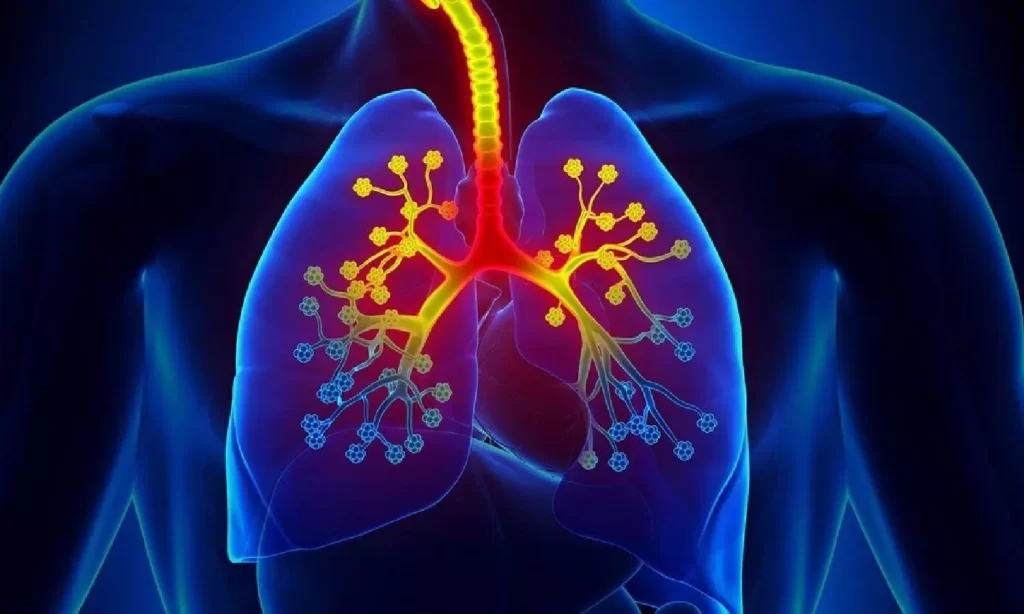

நாட்டில் தற்போது ஆஸ்துமா நோயாளிகளின் எண்ணிக்கை அதிகரித்து வருவதாக சுகாதார பிரிவினர் கூறுகின்றனர்.

உலகளவில் 100,000 பேரில் 3,340 பேருக்கு ஆஸ்துமா இருப்பதாக சுவாச நோய் வைத்திய நிபுணர் ஆஷா சமரநாயக்க தெரிவித்துள்ளார்.

உலகெங்கிலும் உள்ள இளைஞர்களிடையே ஆஸ்துமா பரவலாக இருப்பதாகவும் அவர் சுட்டிக்காட்டுகிறார்.

“இன்ஹேலர்” சிகிச்சையானது பக்க விளைவுகள் இல்லாமல் ஆஸ்துமாவை மிகச் சிறப்பாக குணப்படுத்தும் ஆற்றலைக் கொண்டுள்ளது.

ஆஸ்துமா இருந்தாலும், இந்த நாட்டில் அது கண்டறியப்படாத நோயாளிகள் அதிக எண்ணிக்கையில் உள்ளனர்” என்றார்.